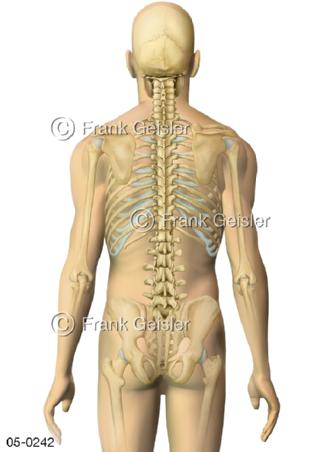

Bildergalerie Skelettsystem

Bilder zum Skelettsystem zeigen die Stützstruktur des menschlichen Körpers, die Knochen, eine besonders harte Form des Bindegewebes und Stützgewebes, welche das menschliche Skelett bildet, die Knochen des Stammes, der Extremitäten sowie der Gelenke